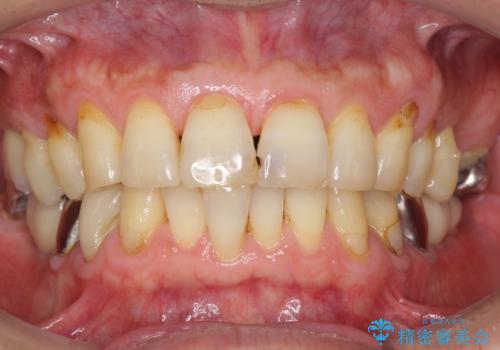

審美的・機能的な仕上がりに喜んで下さいました。

また、半年という比較的短期間でインプラント治療が終わったことにもご満足頂けました。

インプラントの種類:スプライン ツイスト (保証期間:5年)

クラウンの種類:ベレッツァクラウン (オールセラミック)

固定様式:セメント固定